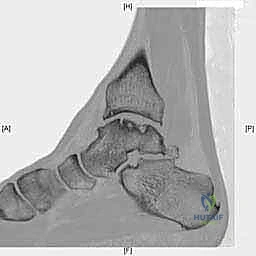

- التصوير المقطعي المحوسب (CT Scan): ضروري جداً للآفات الكبيرة. يوفر الـ CT صورة ثلاثية الأبعاد للعظم، مما يساعد الجراح في التخطيط الدقيق لعملية قطع العظم وحجم الطعم المطلوب زراعته.

لفهم أهمية وصعوبة هذه الجراحة، من الضروري والمهم جداً أن نلقي نظرة طبية دقيقة على تشريح الكاحل. الكاحل ليس مجرد مفصل بسيط، بل هو تحفة هندسية حيوية، مفصل معقد يتحمل وزن الجسم كاملاً بالإضافة إلى قوى مضاعفة أثناء الأنشطة الرياضية. يتكون مفصل الكاحل من التقاء ثلاثة عظام رئيسية:

عظم الكاحل (التالوس): حجر الزاوية

عظم الكاحل هو عظم فريد من نوعه في جسم الإنسان. يتميز بأن الغضروف المفصلي يغطي حوالي 60% إلى 70% من مساحة سطحه الكلية. لا توجد أوتار أو عضلات تلتصق به مباشرة، بل يعتمد بالكامل على الأربطة لتثبيته. إنه بمثابة "حجر الزاوية" في قبو مفصل الكاحل، حيث يتمفصل من الأعلى مع عظم الظنبوب لتكوين المفصل الظنبوبي الكاحلي (Tibiotalar joint)، ومن الداخل مع الكعب الإنسي (Medial Malleolus)، ومن الخارج مع الكعب الوحشي (Lateral Malleolus). هذه الترتيبات الهندسية المعقدة هي التي تسمح بحركة الانثناء الأخمصي والانثناء الظهري (رفع وخفض القدم) الضرورية للمشي والجري.